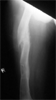

Pre

Op

5 cm right leg due to previous malunited fractured femur. Had Ilizarov lengthening femur done

Femoral lengthening with Ilizarov frame in-situ